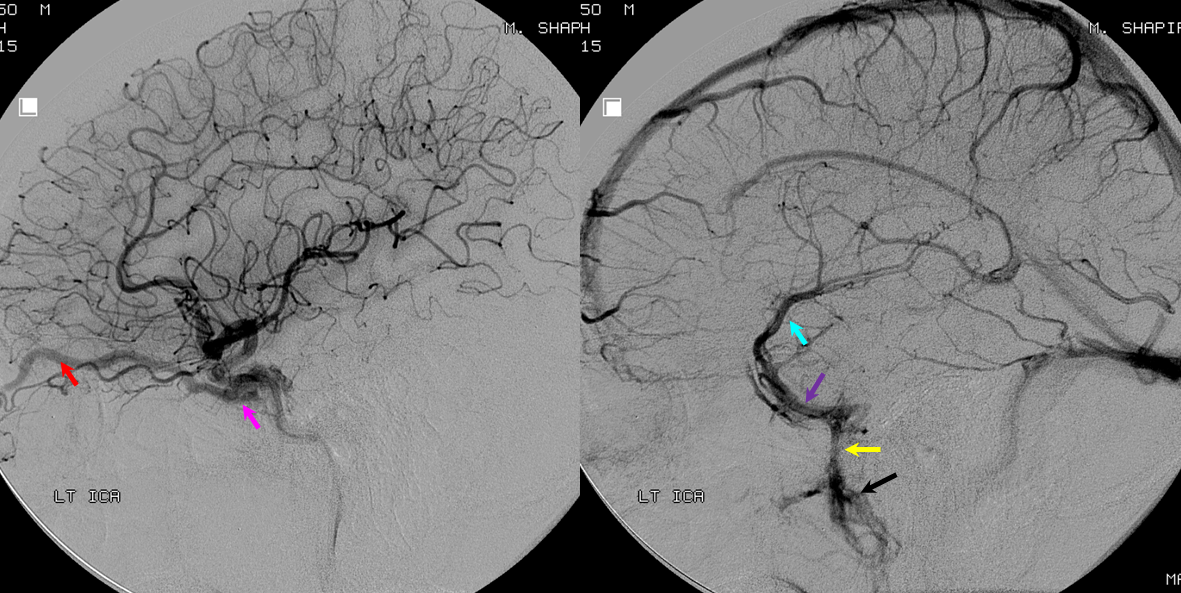

Below is a case of severe venous sinus thrombosis and secondary parenchymal venous infarcts

The explanation for the above tragic pattern is below. On the right, sigmoid and transverse sinuses are patent. However, the Labbe is hypoplastic, and majority of outflow used to go to the Trolard, into the now occluded SSS. There is no other effective way to go — the trolard tries to decompress via a left diploic vein, and convexity tries to access the deep venous system (which normally should not be well-seen in setting of hypoplastic right A1 segment). The left situation is much better, as well-developed superficial sylvian veins drain into the patent Cavernous Sinus. Thus, despite thrombosis of the left transverse and sigmoid sinuses, the left hemisphere is doing better, while the right one, which has patent transverse and sigmoid sinuses, is devastated.

Post venous thrombectomy — with limited results. Note presence of same left diploic vein as seen in right ICA injection, and connection between the distal superior sagittal sinus and the deep venous system via the inferior sagittal sinus.

Sagittal Sinus Thrombosis — collaterals.

All of the above anatomic knowledge can become very useful in evaluation of venous thrombosis. Numerous collateral pathways develop in this setting attempting to compensate for the loss. The most dramatic cases usually involve the largest channel — the superior sagittal sinus. In this case, a man presented with what initially was thought to be vasculitis-related brain hemorrhage. Subsequent workup led to an angiogram, where sagittal sinus thrombosis with extensive trans-cerebral and trans-osseous emissary vein collateral channels was seen. In retrospect, these findings were present on the patient’s earlier contrast MRI. “Venovibe” or other contrast-enhanced MR venograms can very sensitive, particularly when interpreted with the appropriate index of suspicion. Noncontrast 2-D time of flight MRV I consider to be next to useless as a problem-solving technique. Any thin-slice postcontrast T1 study is vastly superior.